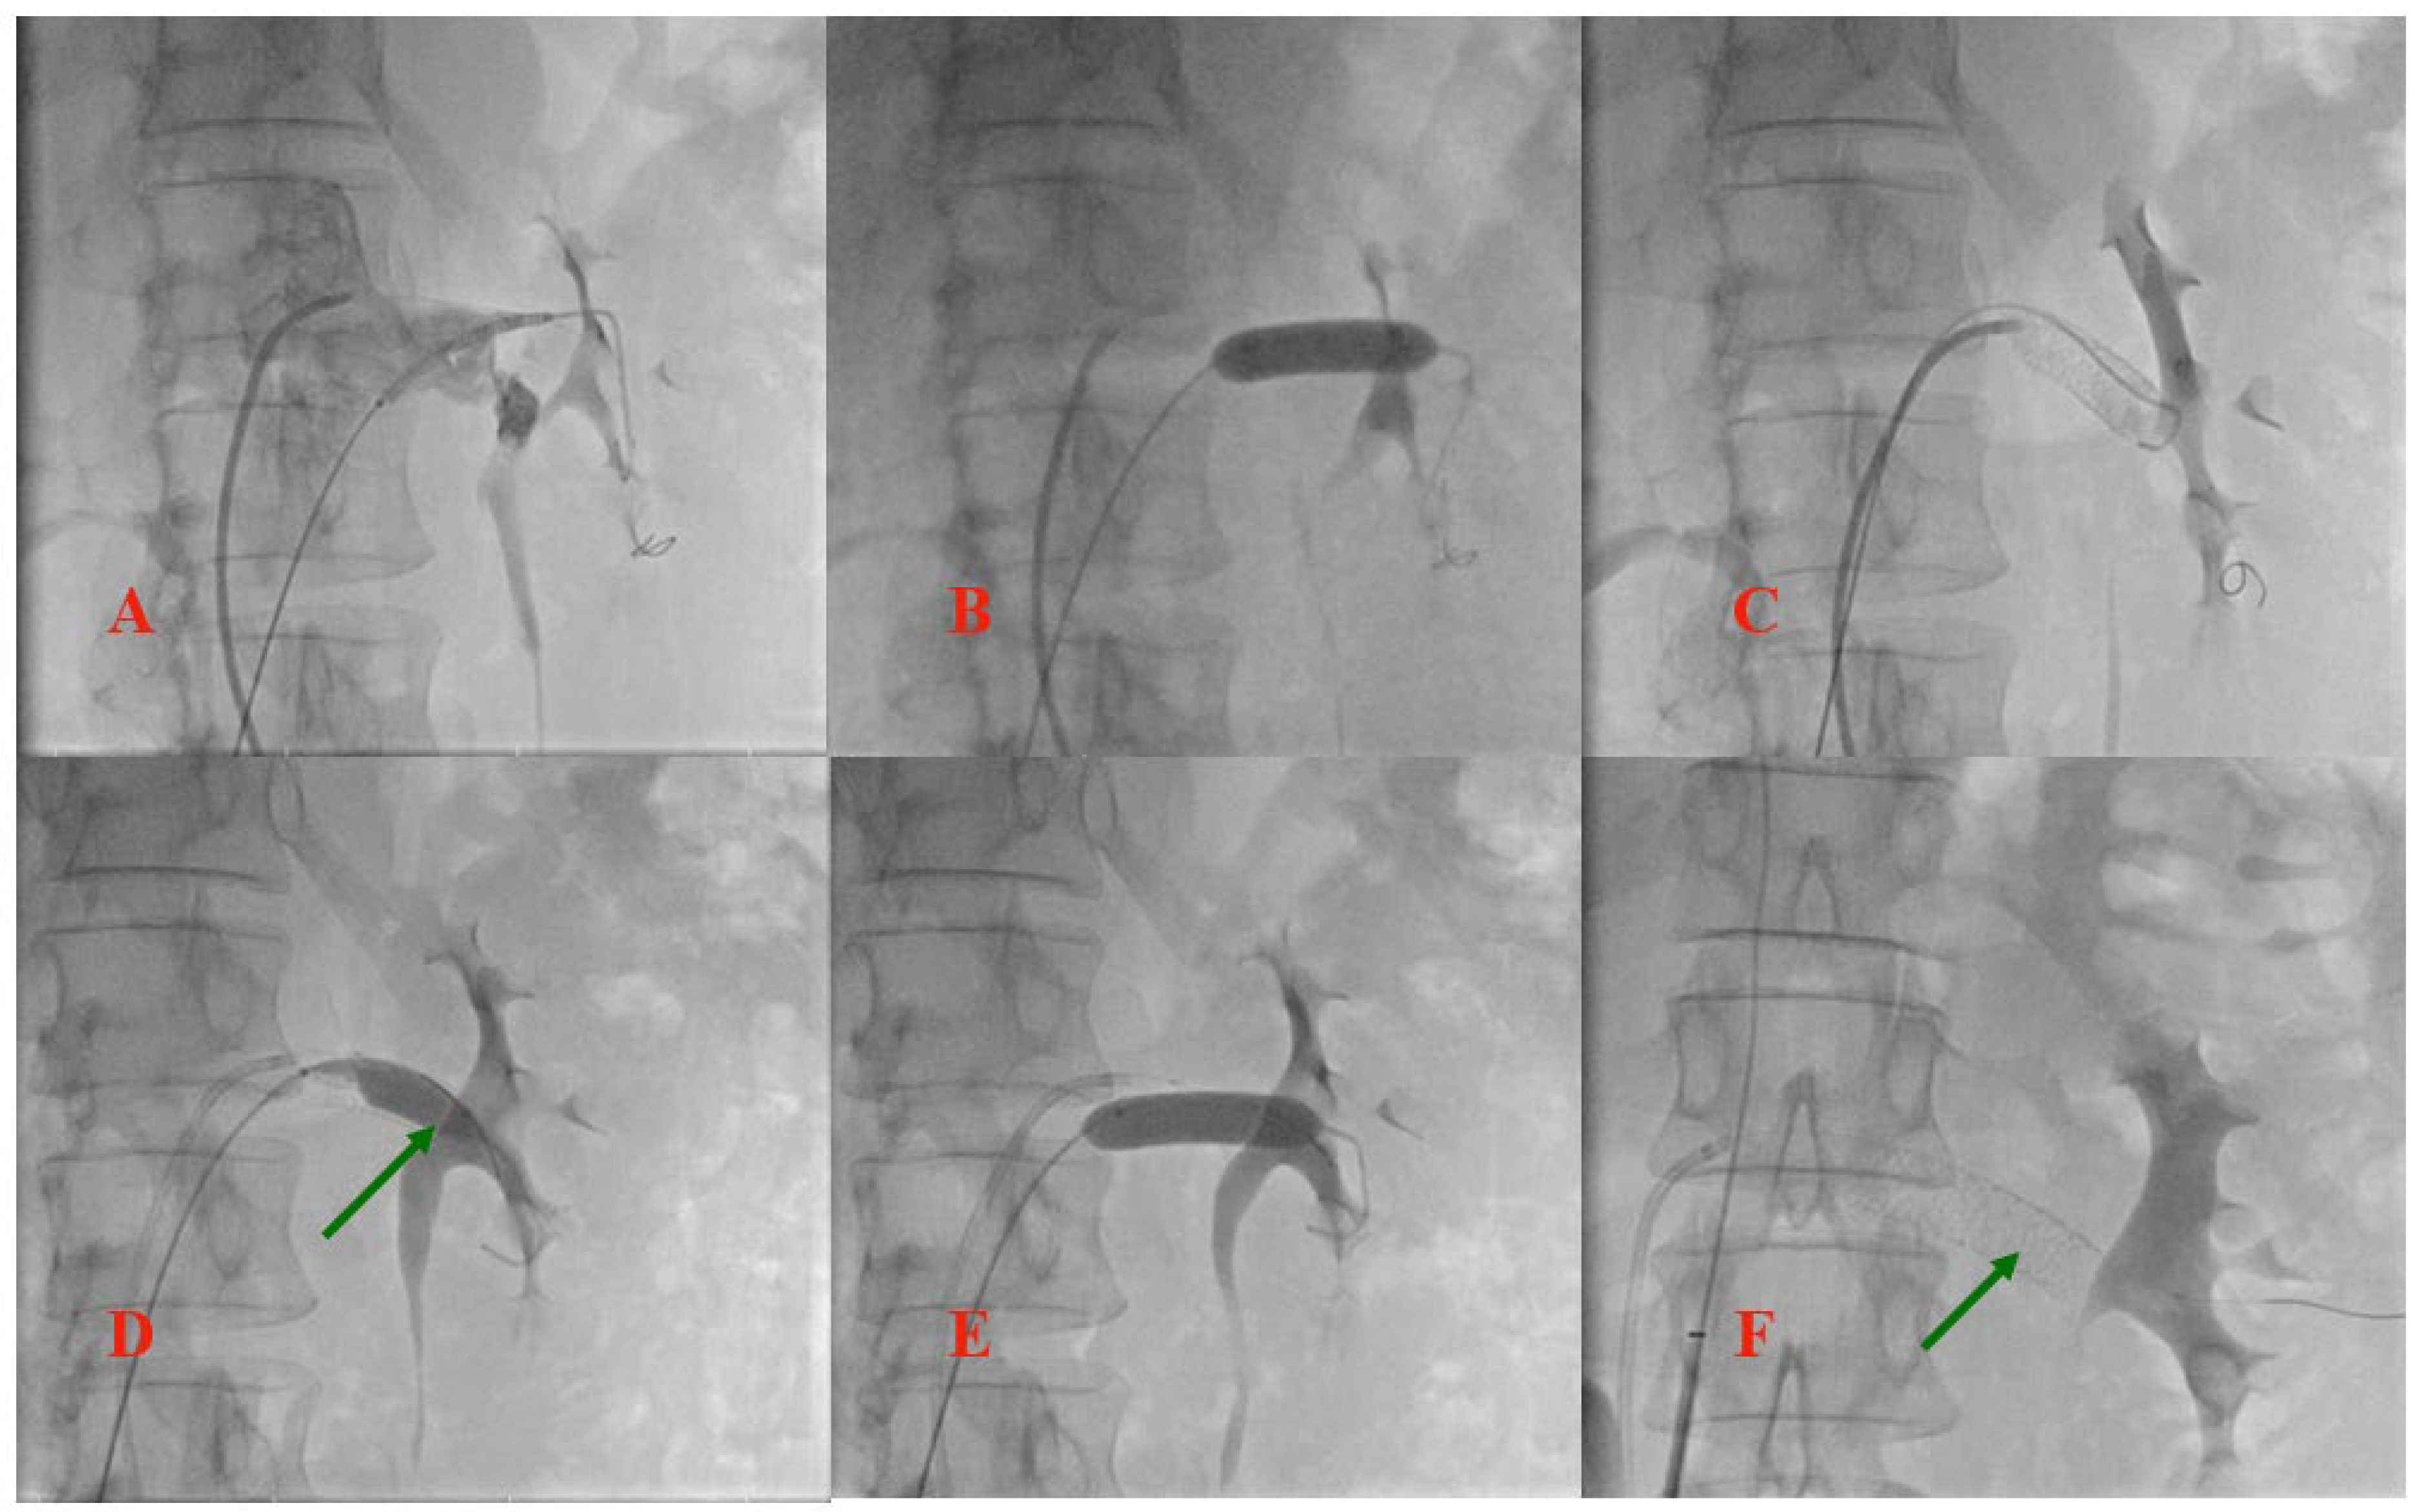

Stent placement in a 16yearold boy presenting with leftside Nutcracker Syndrome Stent Outcomes of left renal vein stenting in patients with nutcracker syndrome. Endovascular stenting for treatment of nutcracker syndrome: Endovascular stenting for treatment of nutcracker syndrome: Nutcracker syndrome (ncs) is a rare condition. Nutcracker syndrome is a rare condition that occurs as a result of the entrapment of the left renal vein (lrv) between the aorta. The nutcracker syndrome is a. Nutcracker Syndrome Stent.